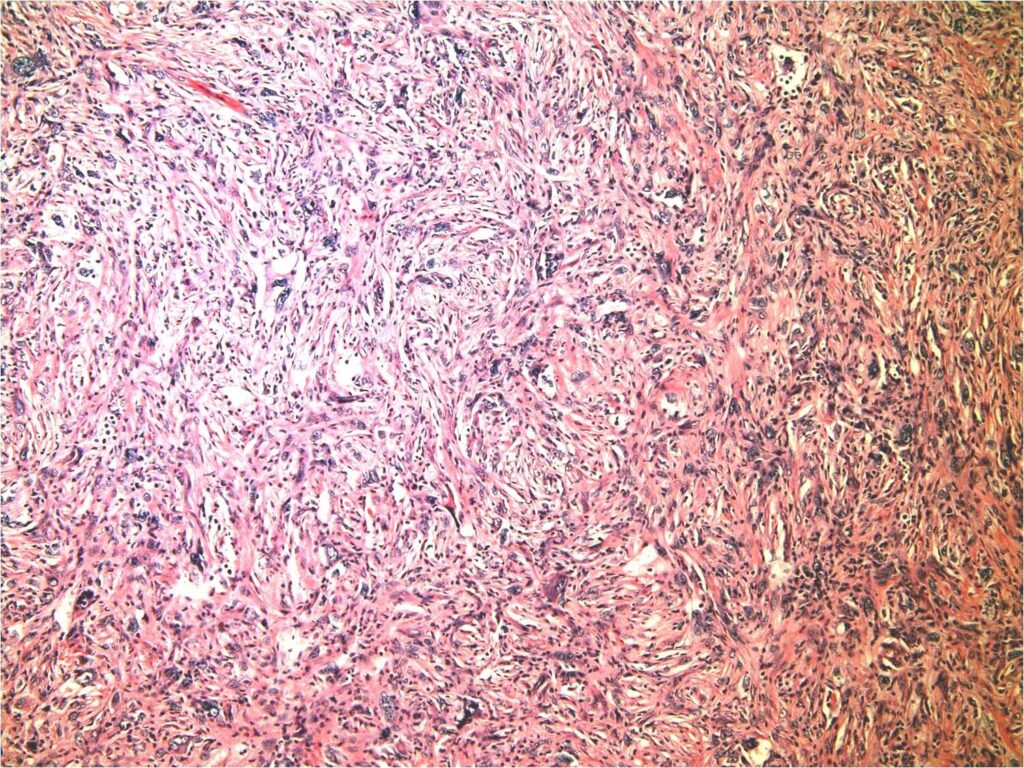

Malignant fibrous histiocytoma of bone is a high-grade spindle cell sarcoma. Microscopically they are heterogeneous fibroblastic tumors formed by poorly differentiated fibroblasts, myofibroblasts, histiocyte-like cells with high degree of pleomorphism, characteristic storiform pattern and also demonstrate bizarre multi-nucleated giant cells (Fig. 7-9).

Fig. 7-9: Microscopic Pathology. Low (Fig. 7), intermediate (Fig. 8) and high (Fig. 9) power magnification H&E slides demonstrate a hypercellular high grade spindle cell sarcoma. Abundant poorly differentiated fibrous tissue is visible in storiform pattern in all magnifications. Multiple giant cells are also seen. Tumor cells are pleomorphic and darkly stained. There are large bizarre appearing cells and atyipical mitotic figures.